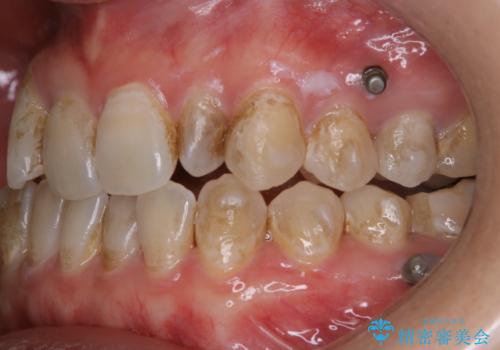

インビザライン矯正中にPMTCでコーヒーによるステインの除去

- コーヒーを毎日頻繁に飲むため、ステインがついてしまうとのことでした。全体的に頑固なステインの付着が見られたため、PMTC60分コースを行いました。

PMTC(保険外治療)は、毎日の歯磨きで落としきれない汚れや、コーヒ、紅茶・タバコのヤニなどの着色も除去します。目には見えない歯と歯の間・歯肉の境目・インビザライン中はアタッチメント周囲などに残っているプラーク(歯垢)もしっかり取り除きます。PMTCでは専門的な機械や材料を使用して、徹底的に汚れを除去するため、虫歯・歯周病・口臭予防などにつながります。

また、仕上げのトリートメントでは歯の表面の凸凹にミネラルを補給して、ツルツルの表面に仕上げます。定期的にPMTCを行うことにより、歯質の強化になり着色がつきにくい状態になります。